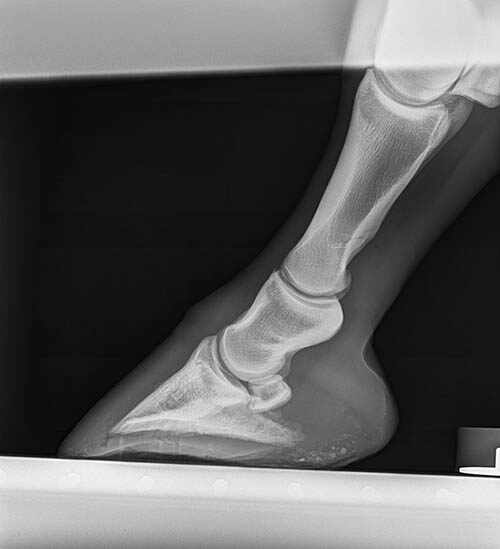

The benefit of a harmonious relationship is evident in a case I saw recently where I was able to work as a team with the farrier and the outcome was great for everyone. The patient was a three-year-old thoroughbred gelding that was 2/5 lame in his left front leg, and I was able to localise the lameness to the foot. The farrier was consulted and he took over the management of the lameness, although I stayed in close contact with the owners to follow the horse’s progress.

The lameness improved under the farrier’s care initially but returned about a week or so later. An abscess or an under-run sole due to an infection was suspected, but with pain around the whole foot, the farrier could not isolate an area on the sole to dig into and relieve the pressure. Despite daily bathing of the foot and hot poultices applied, the horse remained lame with no sign of an abscess tracking out of the foot.

As I had a great relationship with the farrier, we discussed the case and decided the best approach was to work together to find a solution. I was able to X-ray the foot with the farrier present and isolate a small pocket of pus (gas pocket) near the toe of the foot. The farrier was able to cut the tip of a horseshoe nail and fix it to the area of the sole that we both thought approximated the underlying gas pocket. By X-raying again and adjusting our marker, we were able to accurately pinpoint an area and the farrier was able to make a small hole directly over the abscess and allow the pus to escape. The result was a horse that was significantly sounder (and happier) the following day.